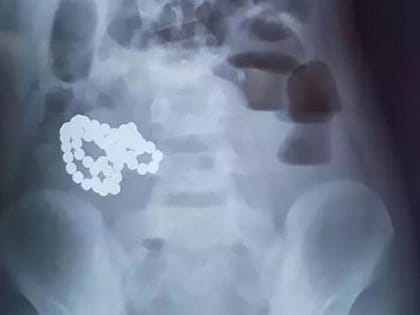

Голодный до золота. Южноуралец «проглотил» ювелирные изделия соседа по больничной палате

Как сообщает пресс-служба ГУ МВД России по Челябинской области, в Миассе полицейские задержали 40-летнего гражданина, проглотившего ювелирные изделия соседа по больничной палате.